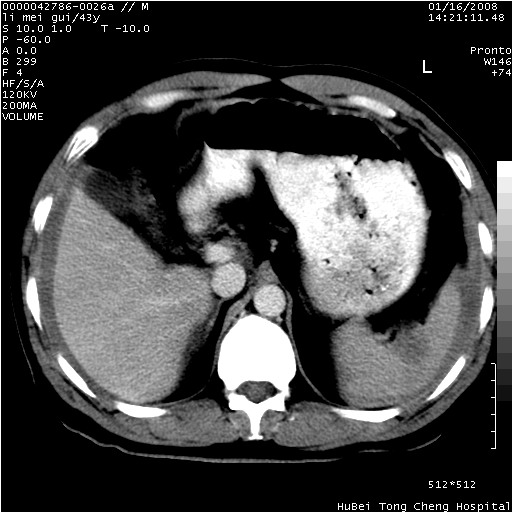

| 患者,男,43岁。突发腹痛2小时,面色苍白,难以平卧。自述近期无明确外伤史,为摩托车驾驶员。 腹部b超检查:脾脏中上极回声异常,肿瘤待排。 临床诊断:腹痛原因待查。 上中腹部ct轴位平扫+增强扫描(层厚10mm,螺距1.0,重建间隔10mm),图像如下: ![]() ![]() ![]() ![]() ![]() ![]() ![]() ![]() ![]() ![]() ![]() ![]() ![]() ![]() ![]() ![]() ![]() ![]() ![]() ![]() ![]() ![]() ![]() ![]() ![]() ![]() ![]() ![]() ![]() ![]() ![]() ![]() ![]() ![]() ![]() zrs发言:支持脾破裂 wwp发言:支持脾破裂并腹水。 xulianj发言:脾脏肿瘤破裂可能性大 zsl6918发言:不像肿瘤出血,考虑还是与外伤后引起的慢性出血有关 zzyy发言:平扫见肝周及脾周积液,脾内密度不均。脾内肿瘤较少见。还是外伤性脾破裂。 沈丘东方医院发言:脾门区一个不均匀强化病灶与其周液体相连多考虑脾占位破裂出血 yixianman001011发言:脾破裂并腹水是可以肯定的,具体原因多以肿瘤性破裂出血,脾脏淋巴瘤可能性大. 结果: 术后,经详细询问患者,其仔细回忆:一月前骑摩托时左侧腰部与别人有“轻微”触碰,因责任在自已,当时又无明显不适,未引起注意。 临床术后诊断:脾破裂并失血性休克(1.外伤性迟发性脾破裂。2.脾脏肿瘤破裂?) 术后标本病检:脾破裂并出血,未见明显肿瘤成份。 原贴地址:http://www.radinet.com.cn/forum_view.asp?forum_id=4&view_id=34070 |